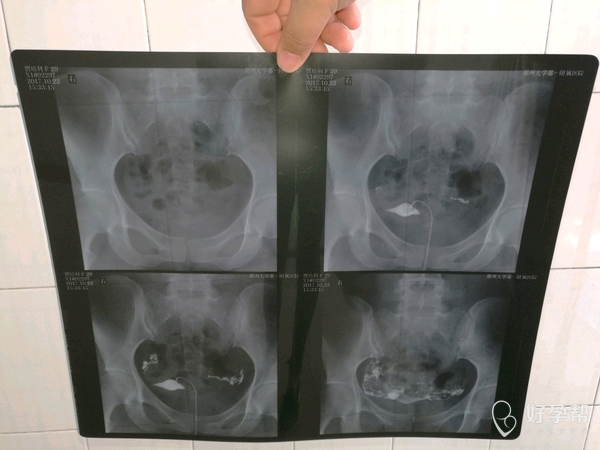

月经第十天右侧卵泡15*13 内膜7.5

你好,右侧输卵管问题需要解决,否则即使有好卵泡,也不好受孕